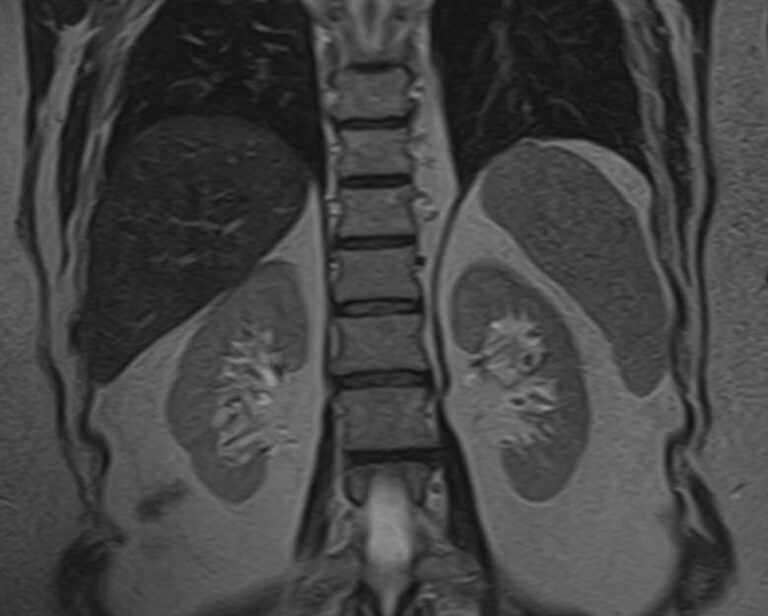

МРТ забрюшинного пространства является наиболее информативным, безопасным и доступным методом исследования, который позволяет оценить состояние органов, расположенных в данной анатомической зоне (почки, надпочечники, мочеточники), выявить возможные патологические процессы.

В клинике «Доступная медицина» установлен новейший высокопольный томограф экспертного уровня TOSHIBA VANTAGE TITAN 1,5 Тесла, на котором выполняется обследование органов забрюшинного пространства. За счет высокой индукции магнитного поля аппарат при сканировании создает изображения на плоскости превосходной четкости, затем с помощью компьютерных приложений данные преобразуются в изображения трехмерного формата, что обеспечивает точность и достоверность диагностики.

МРТ брюшного и забрюшинного пространства направлено на определение состояния нескольких органов, по результатам диагностики визуализируют:

- Почки. С помощью магнитно-резонансной томографии удается диагностировать структурные изменения. Аномалии развития, воспалительные процессы, изменение нормального расположения в забрюшинном пространстве.

- Надпочечники. Парный орган эндокринной системы. Из-за особенностей анатомии, строения, трудно визуализируются прочими способами. МРТ позволяет получить детальную картину изменений надпочечников.

- Мочеточники. Часть мочевыделительного тракта. Из-за малого диаметра и особенностей строения, визуализируются с трудом. Томография — основной способ диагностики патологических процессов.